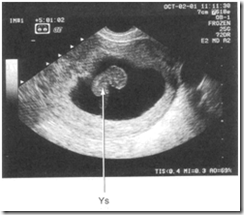

USG transvaginal dapat digunakan untuk deteksi kehamilan 4 – 5 minggu.

Detik jantung janin terlihat pada kehamilan dengan CRL > 5 mm (usia kehamilan 5 – 6 minggu).

Dengan melakukan dan menginterpretasi secara cermat, pemeriksaan USG dapat digunakan untuk menentukan apakah kehamilan viabel atau non-viabel.

Pada abortus imimnen, mungkin terlihat adanya kantung kehamilan (gestational sac GS) dan embrio yang normal.

Pada missed abortion, terlihat adanya embrio atau janin tanpa ada detik jantung janin.

Pada blighted ovum, terlihat adanya kantung kehamilan abnormal tanpa yolk sac atau embrio

Kehamilan intrauterine 8 minggu. Terlihat gambaran embrio (E) dan yolk sac (YS)